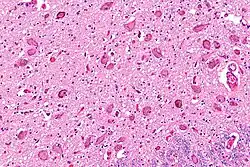

The locus coeruleus (LC) is located in the posterior area of the rostral pons in the lateral floor of the fourth ventricle. It is composed of mostly medium-size neurons. Melanin granules inside the neurons contribute to its blue colour. Thus, it is also known as the blue nucleus, or the nucleus pigmentosus pontis (heavily pigmented pontine nucleus).[5] The neuromelanin is formed by the polymerization of norepinephrine and is analogous to the black dopamine-based neuromelanin in the substantia nigra.

In adult human males,[a] the locus coeruleus has 22,000 to 51,000 total pigmented neurons that range in volume from 31,000 to 60,000 μm3.[6]

The locus coeruleus is affected in many forms of neurodegenerative diseases: genetic and idiopathic Parkinson's disease, progressive supranuclear palsy, Pick's disease, and Alzheimer's disease. It is also affected in Down syndrome.[29] For example, there is up to 80% loss of locus coeruleus neurons in Alzheimer's disease,[30] Mouse models of Alzheimer's disease show accelerated progression after chemical destruction of the locus coeruleus.[31] Neurofibrillary tangles, a primary biomarker of Alzheimer's disease, may be found in the locus coeruleus decades before any clinical symptoms.[32] The norepinephrine from locus coeruleus cells in addition to its neurotransmitter role locally diffuses from "varicosities". As such it provides an endogenous anti-inflammatory agent in the microenvironment around the neurons, glial cells, and blood vessels in the neocortex and hippocampus.[18] It has been shown that norepinephrine stimulates mouse microglia to suppress Aβ-induced production of cytokines and promotes phagocytosis of Aβ.[18] This suggests that degeneration of the locus coeruleus might be responsible for increased Aβ deposition in AD brains.[18] Degeneration of pigmented neurons in this region in Alzheimer's and Parkinson's disease can be visualized in vivo with Neuromelanin MRI.[33] Since the marked degeneration of locus coeruleus, and the neuroprotective properties of noradrenaline, Ian Robertson proposed the "Noradrenergic Theory of Cognitive Reserve" [34] which postulates that the upregulation of the locus coeruleus-noradrenergic system throughout the lifespan may enhance cognitive stimulation contributing to cognitive reserve preventing from neurodegeneration. Evidence appear to support this theory reporting the locus coeruleus integrity primarily responsible of biological brain maintenance,[35][36][37] including brain clearance,[38] cognitive efficiency, and reduced neuropathological burden.[35][39][40][41]